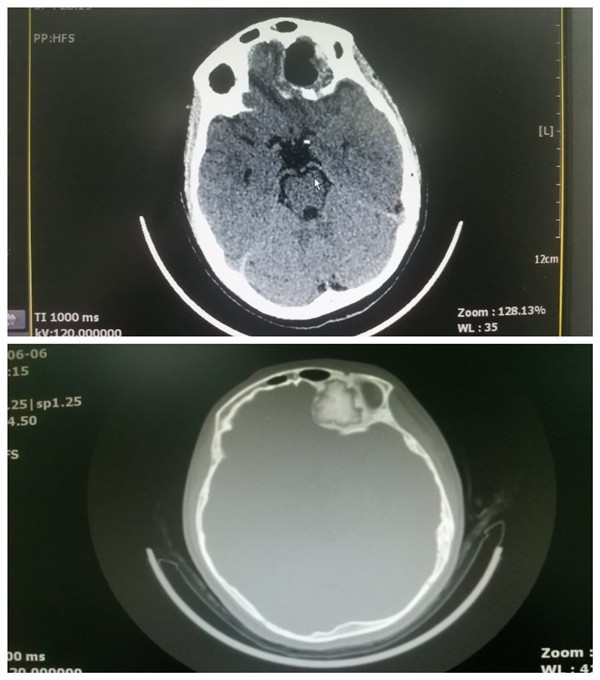

术前术后CT比较